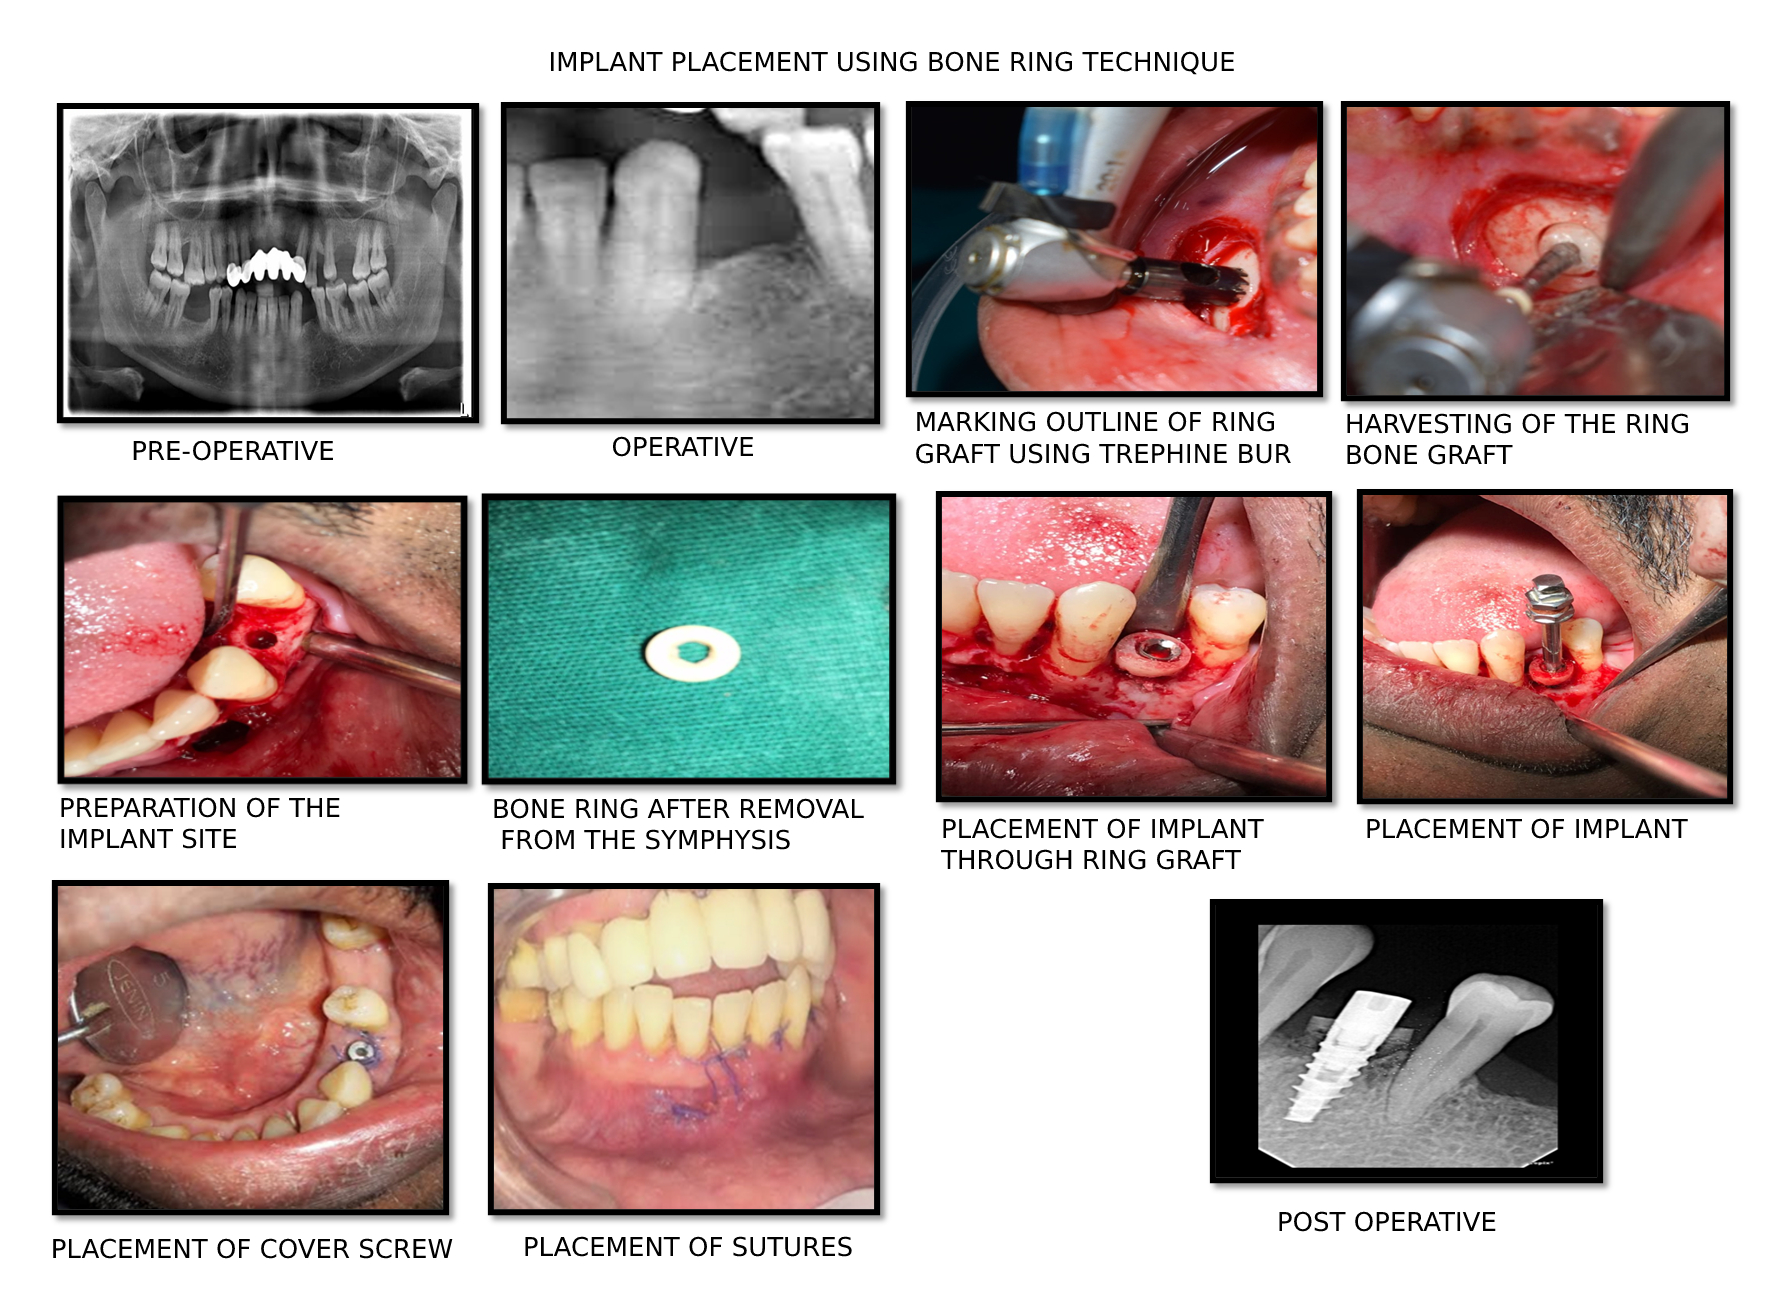

- PRAGATI MODI , secured 1st prize for paper presentation on Augmentation of implant site using ring bone graft – a case report in the 17th isp convention 2018-2019, Chennai.

| Dr. Pragati Modi | Paper On Augmentation Of Implant Site Using Ring Bone Graft – A Case Report | Ist in session |